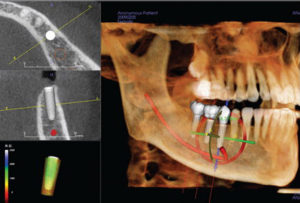

With the growing popularity of implants, many dentists are exploring ways to add this type of procedure to their treatment options. When implants are indicated, the process of determining the optimal treatment plan starts even before the details of the implant itself are considered. The opportunity to view a three-dimensional scan of my patient’s anatomy before starting an implant makes me a better dentist. My i-CAT® provides me with better visualization and a clearer perspective on my options. Most importantly, CBCT gives me the ability to achieve my desired results more easily and less stressfully.

Not only do 3-D images prepare the dentist for surgery, they help the doctor educate the patient to the inevitability, and not just the possibility, for certain pre-implant necessities such as bone grafting. I can use the data garnered from cone-beam scans in conjunction with third-party software such as SimPlant®, EasyGuide™, NobelGuide™, and InVivo5™ to create precise treatment plans and surgical stents for even more accurate implant placement.

The “surgical view” that cone-beam imaging offers has become an integral part of my implant process. I also believe that it is important to use cone beam not so much as a “Standard of Care,” but more for “Appropriateness of Care.” It is our responsibility as dentists to provide appropriate treatment based on the individual’s distinct lifestyle and specific dental issues. I use my cone beam to discern the best course of treatment for that particular patient, such as, whether to propose an implant or a conventional bridge.